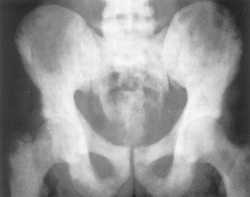

Radiografia articulatiilor sacroiliace evidentiaza osteoporoza subcondrala a suprafetelor articulare care devin neregulate, cu limite sterse, difuze cu spatiul articular largit. Osteoporoza se extinde la sacru si osul iliac pe care apar si mici zone de osteoliza (geode) rezultând un aspect tigrat al regiunii. Ulterior apare osteoscleroza a suprafetelor articulare, spatiul se îngusteaza pâna la anchiloza completa sacroiliaca. Leziunile sunt bilaterale simetrice.